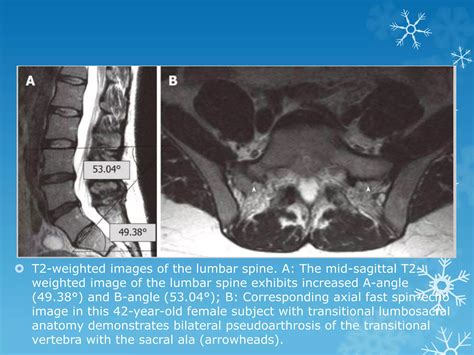

Diagnostic Imaging and Identification

Radiology plays the most critical role in diagnosing Transitional Lumbosacral Anatomy. Standard X-rays of the lumbar spine are often the first step, but they may not provide enough detail to distinguish between a fusion and a complex articulation. In more complex cases, Computed Tomography (CT) scans or Magnetic Resonance Imaging (MRI) are utilized to provide a three-dimensional view of the lumbosacral region.

Radiologists utilize a method called vertebral counting, starting from the C2 vertebra in the neck and moving down through the thoracic spine to determine the exact level of the LSTV. This rigorous process ensures that the patient's anatomy is correctly mapped, preventing miscommunication between the imaging department and the orthopedic surgeon.